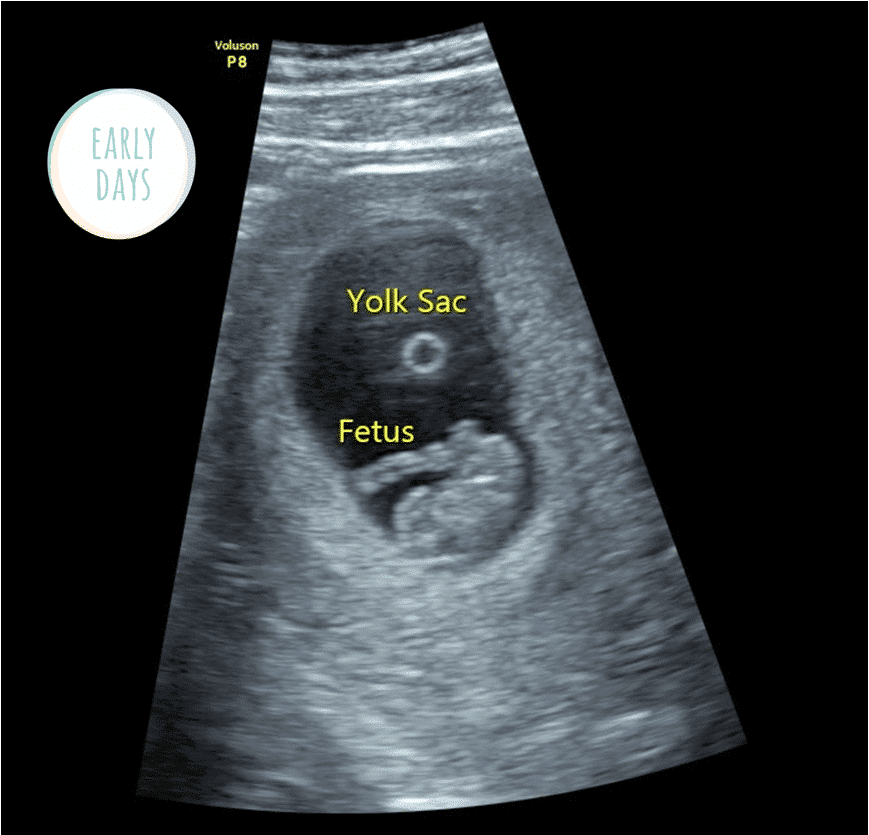

The early stages of pregnancy (0-16 weeks) – Your Baby Scan

Baby’s growth at 6 weeks pregnant through ultrasound pictures …

First trimester Ultrasound Sonogram Scans week by week early scan …